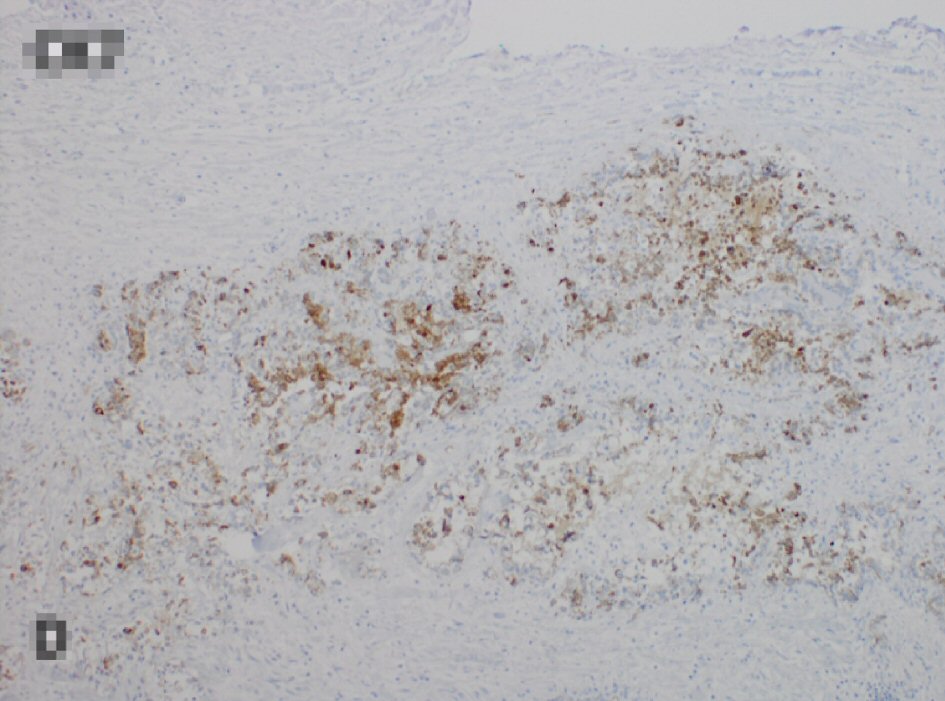

After obtaining the CT scan, the patient was admitted to the hospital ward for further management. The general surgery and gastroenterology services were consulted for recommendations. Initially an endoscopic placement of a palliative colonic stent was attempted but given the size of the lesion this was not amenable. General surgery then took the patient to the operating room and performed an en bloc resection of the colonic mass which was adherent to the transverse colon. The resected specimen was then sent to our pathologist for further evaluation. The results of the specimen showed metastatic adenocarcinoma consistent with gastric origin. This diagnosis was supported by cell positivity to cytokeratin (CK)7 and negativity to CK20 and CDX2 (Figs. 2, 3).

![]() Click for large image | Figure 3. Tumor cells staining positively to CK7 and negative for CK20 and CDX2 (not shown), consistent with gastric origin. CK: cytokeratin. |